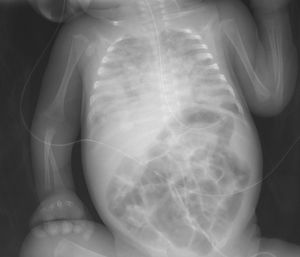

The rarity of some infectious diseases in newborns causes a delay in diagnosis, leading to high morbidity and mortality rates. We present the case of a premature infant of 28 weeks gestational age, with healthy parents of Roma ethnicity, who was admitted to the neonatal unit due to prematurity and had been making good progress. At 57 days of life, close to hospital discharge, the infant developed severe respiratory distress along with fever, hepatosplenomegaly and clotting abnormalities. A diagnosis of nosocomial sepsis-pneumonia was made, but the patient had a poor clinical and radiological response (Fig. 1) to the usual antibiotic therapy, with a finding of extensive bilateral necrotising pneumonia on computed axial tomography. Secondary haemophagocytic syndrome was suspected as six of the eight clinical-analytical criteria were met.1 Fifteen days after the onset of the condition, due to the poor clinical progress and the negative results of the microbiological tests for viruses, fungi and common bacteria, screening was performed for tuberculosis infection. Samples of gastric juices were taken for three consecutive days for polymerase chain reaction (PCR), sputum smear and culture testing, and a tuberculin skin test (TST) was performed. As the TST reading was negative at 48 h, an interferon-gamma release assay (IGRA) test was requested. The sputum smear microscopy and the PCR in gastric juices were positive for Mycobacterium tuberculosis and the IGRA was also positive. Perinatal tuberculosis (TB) was diagnosed, and a positive culture for M. tuberculosis was subsequently obtained. Contact tracing of family members and healthcare personnel revealed bacillary pulmonary tuberculosis in both the mother and the grandmother. Both reported being asymptomatic and denied travelling abroad.

Radiological findings are very common in infants, particularly hilar lymphadenopathy and miliary pattern. Clinical signs vary, ranging from well-appearing patients with mild respiratory distress to severe respiratory distress, pneumonia unresponsive to treatment, pertussis-like cough, fever, hepatosplenomegaly, lymphadenopathy, abdominal distension, ascites, persistent diarrhoea or jaundice.6 The fundus should be examined for chorioretinitis and granulomas. There are rare manifestations of congenital TB, such as skin or middle ear lesions.7 Without treatment, 10–20% will develop disseminated forms (meningitis or miliary dissemination). It is also more common to develop other complications such as septic shock, disseminated intravascular coagulation, multiorgan failure or haemophagocytic syndrome.